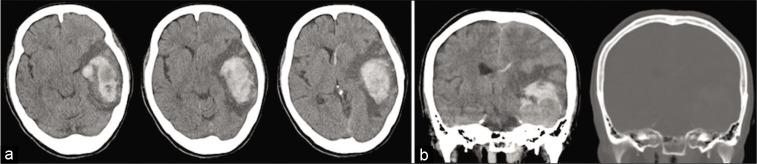

Intracranial and central nervous system's involvement with multiple myeloma (MM) is a clinically rare manifestation. Furthermore, the development of intracranial plasmacytoma without bone involvement is much rarer. Herein, we report the case of massive intracerebral hemorrhage form intracranial plasmacytoma that arose from the dura mater without bone involvement.

A 71-year-old woman, who had been diagnosed as MM and treated 2 years prior, developed sudden lethal intracerebral hemorrhage from the intracranial plasmacytoma. Massive hemorrhage was observed after a rapid tumor growth in the middle fossa. Immediate hematoma evacuation and tumor resection allowed the patient to avoid severe neurological deficits and lethal conditions.

颅内及中枢神经系统受累于多发性骨髓瘤(MM)是一种临床罕见的表现。此外,无骨受累的颅内浆细胞瘤的发生更为罕见。在此,我们报告一例起源于硬脑膜且无骨受累的颅内浆细胞瘤导致大量脑出血的病例。

一名71岁女性,2年前被诊断为MM并接受治疗,因颅内浆细胞瘤突发致死性脑出血。中颅窝肿瘤快速生长后出现大量出血。立即进行血肿清除和肿瘤切除使患者避免了严重的神经功能缺损和致命情况。